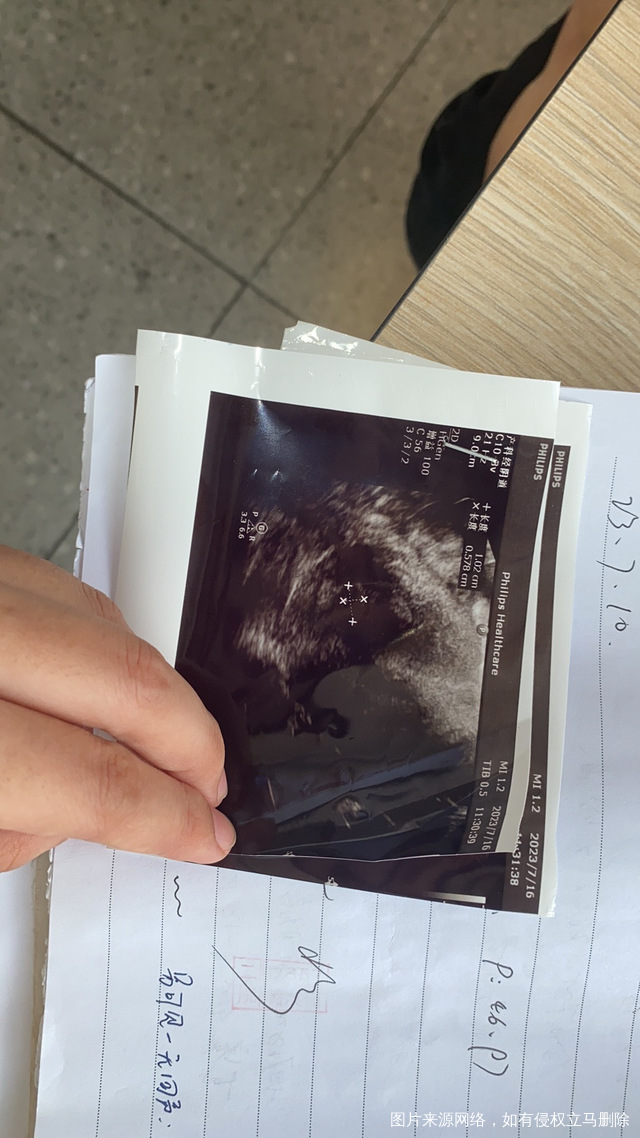

移植第二十天去医院做阴道彩超宫内1006和0